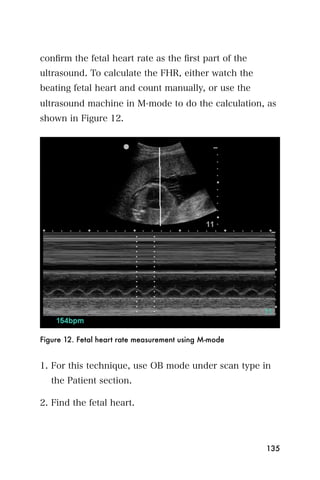

can be used to measure the fluttering of a fetal

heartbeat, as shown in Figure 8.

Figure 8. M mode allows measurement of fetal heart rate.